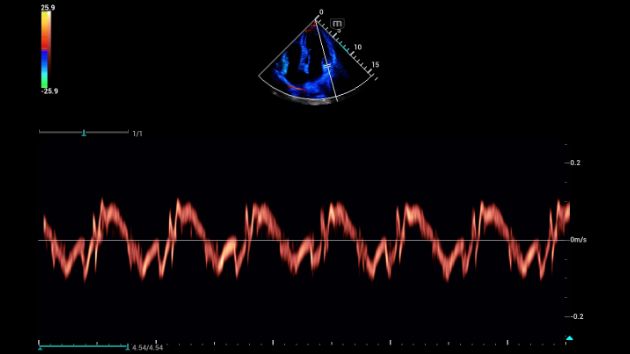

Consona presenta soluzioni nuove e concrete, che aiutano a effettuare diagnosi efficaci con semplicitĂ , rivolgendosi a un'ampia platea di pazienti. La serie mette a disposizione strumenti estremamente avanzati per rimanere all'avanguardia nella diagnosi cardiovascolare.

Galleria di immagini